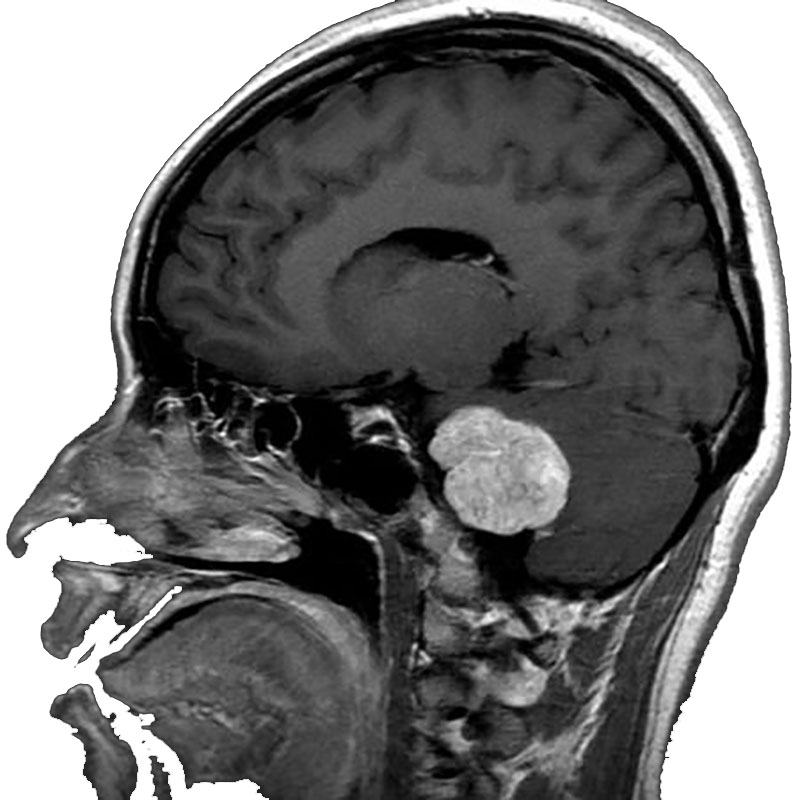

脳動静脈奇形

血管塞栓術

松田/濵田/元永